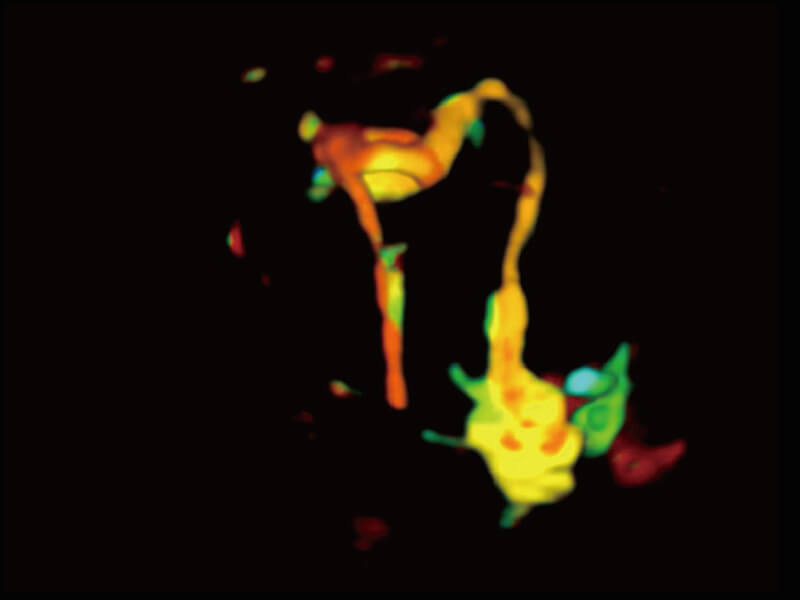

成像功能

超宽频带技术,为容积成像带来优质的二维图像基础,为您呈现丰富的结构细节,栩栩如生地展示宝宝的宫内形态以及各种组织的立体结构。